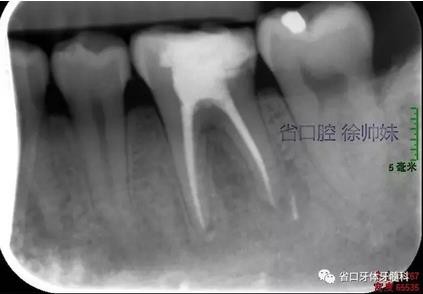

現(xiàn)病史:6個月前左下后牙區(qū)牙齦腫脹,反復溢膿,無明顯其他不適。4月前于我院牙體牙髓科(圖1)就診,診斷為“36牙周牙髓聯(lián)合病變”,建議試行36根管治療+牙周治療保留患牙,患者當時未行治療?,F(xiàn)再次來我院牙體牙髓科要求進一步診治。

圖1 術(shù)前4月的根尖片

根尖片(圖2)示36大面積充填物近髓,根尖周及根分叉大面積低密度影。

圖2 術(shù)前根尖片